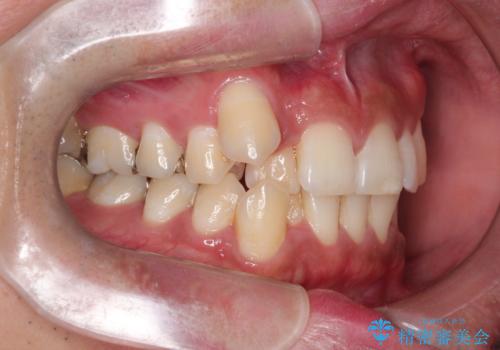

【ワイヤー矯正】八重歯と下の歯の凸凹を治したい

- 主訴:右上の八重歯と、下の歯の凸凹を治したい

上顎右側第一小臼歯と下顎右側第一小臼歯を抜歯しワイヤー矯正を行いました。

右側2級、左側1関係だったため、右側上下第一小臼歯を抜歯し、ワイヤー矯正を行いました。